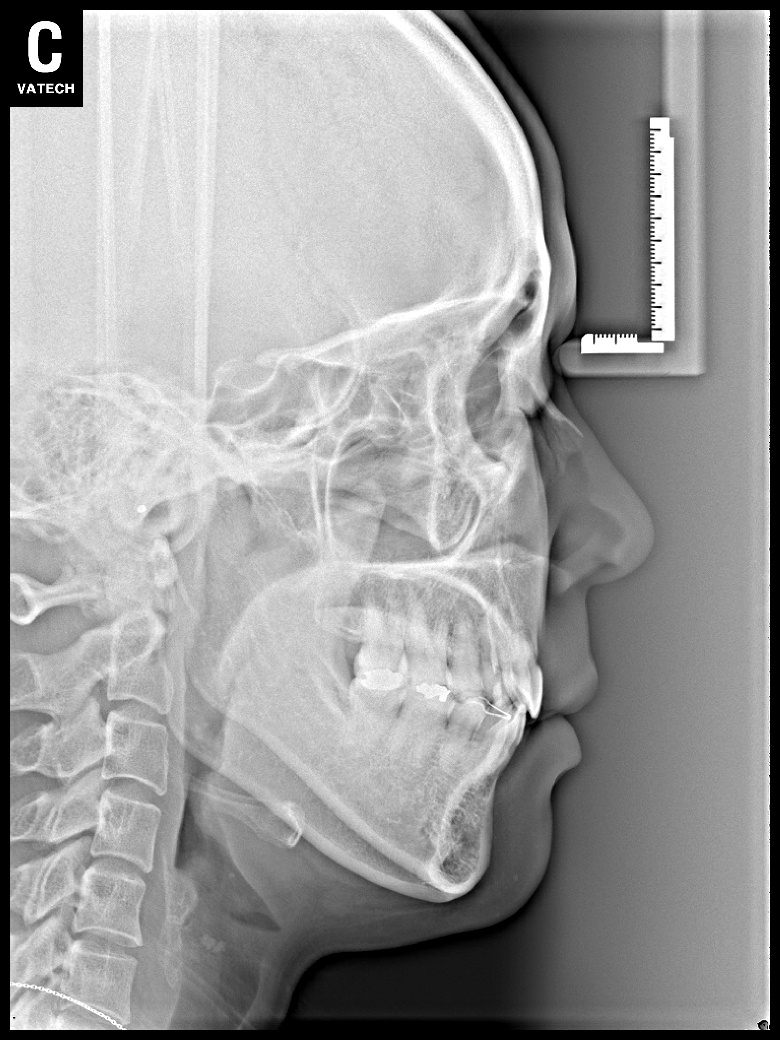

치료 전 사진입니다.